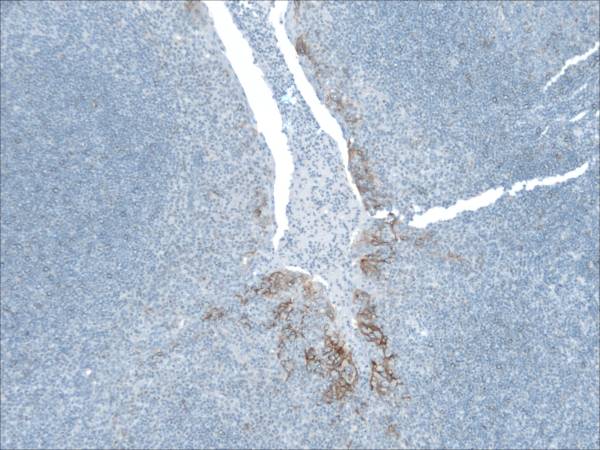

PDL1 Expression by Squamous Epithelium (Tonsil) protecting itself within a cryptitis

At low magnification (Left), one sees the heterogeneous expression of PDL1 in a tonsil which is used as a preferred positive on-slide control for PDL1. This expression is explained by a focal invasion of T cells reaching an infectious area (Center: DAB: CD3, RED: Cytokeratin). The T cells release Interferon-Gamma which stimulates local expression of PDL1 by the epithelium. The right picture shows PDL1 expression at higher magnification.